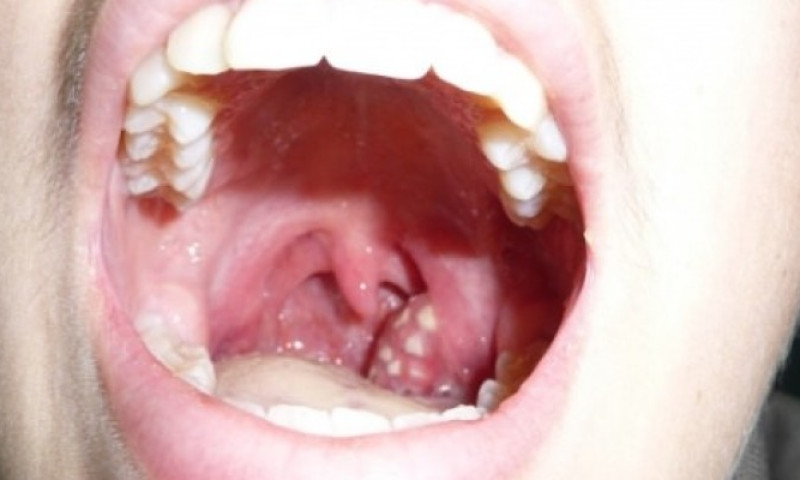

के हो टन्सिलको संक्रमण ? बारम्बार टन्सिल देखिए के गर्ने ?

टन्सिलको संक्रमण

यदि तपाईंलाई एक–दुईपटक मात्र टन्सिलको समस्या देखिएको छ भने चिकित्सकको सल्लाह लिएर घरमै सामान्य एन्टिबायोटिक खाँदा हुन्छ । तर, खाना निल्न र श्वास फेर्न नै गाह्रो भएको छ भने अस्पतालमा बसेर इन्जेक्सनबाट औषधि लगाउनुपर्ने हुन्छ । जटिल खालको र धेरैपटक दोहोरिएको छ वा दुई वर्षदेखि पटक–पटक देखिइरहेको छ भने अप्रेसन गरेर टन्सिल निकाल्नु नै राम्रो हुन्छ । त्यसरी निकालिसकेपछि पुनः टन्सिल हुने सम्भावना हुँदैन । अन्य कारणले भने घाँटी दुख्नसक्छ । टन्सिल निकालेपछि अन्य कुरालाई असर पर्दैन । कतिपय मानिस स्वर भासिन्छ भन्छन्, तर त्यो सत्य होइन । टन्सिल बिग्रिएर भासिएको स्वर निको भएपछि आफैँ ठीक हुन्छ ।